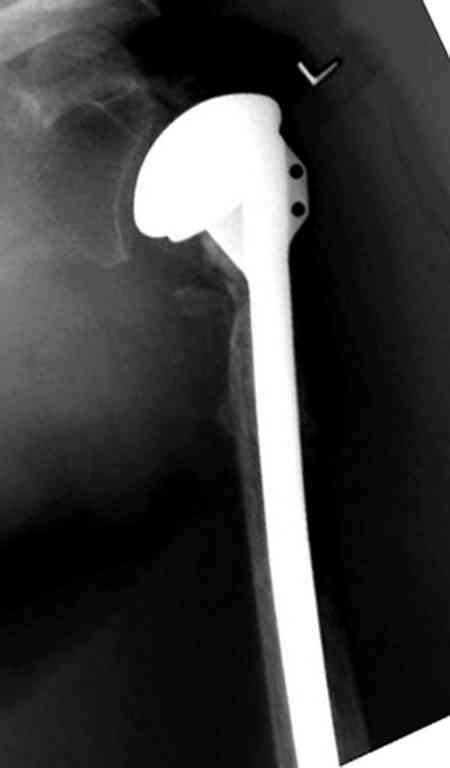

Сделали напряженными спицами по методике А.Ф.Лазарева со товарищи Репозиция сделана спицевым дистрактором, проксимальная спица была проведена в полскости деформации перпендикулярно оси наклонившейся головки. Получилось все довольно легко. Спицы малость покороче можно было сделать, ну да удалять потом легче будет.

Картинка в приложении.

Очень даже неплохо получилось. Молодцы! Лучше чем на 3D "репозиции".

Все заняло 1 час. Собственно введение фиксаторов - минут 20.

Оставили в косынке, сразу разрешены маятникообразные движения в плечевом суставе. Дальше по ходу расскажу.